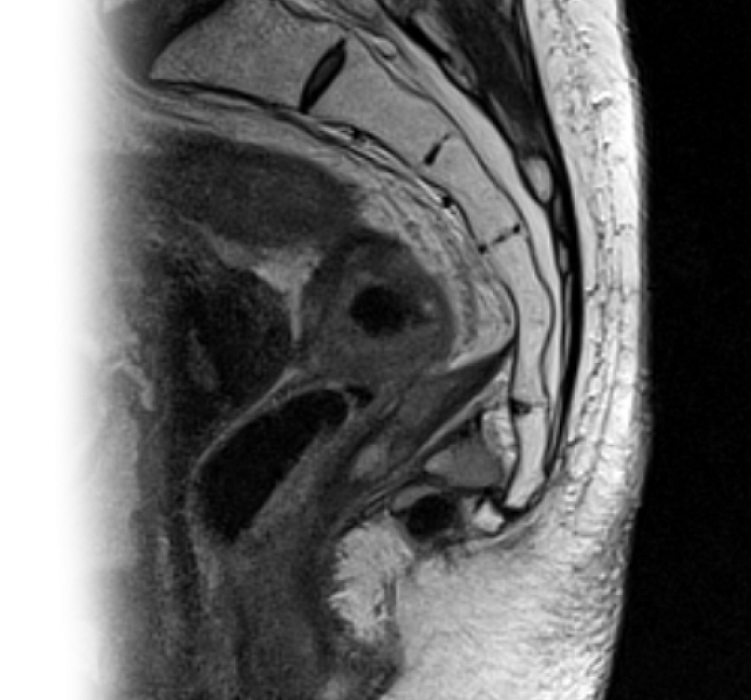

МРТ крестцово-копчикового отдела позвоночника

Магнитно-резонансная томография крестцово-копчикового отдела позвоночника – важный метод исследования, который позволяет оценить состояние крестца и копчика.